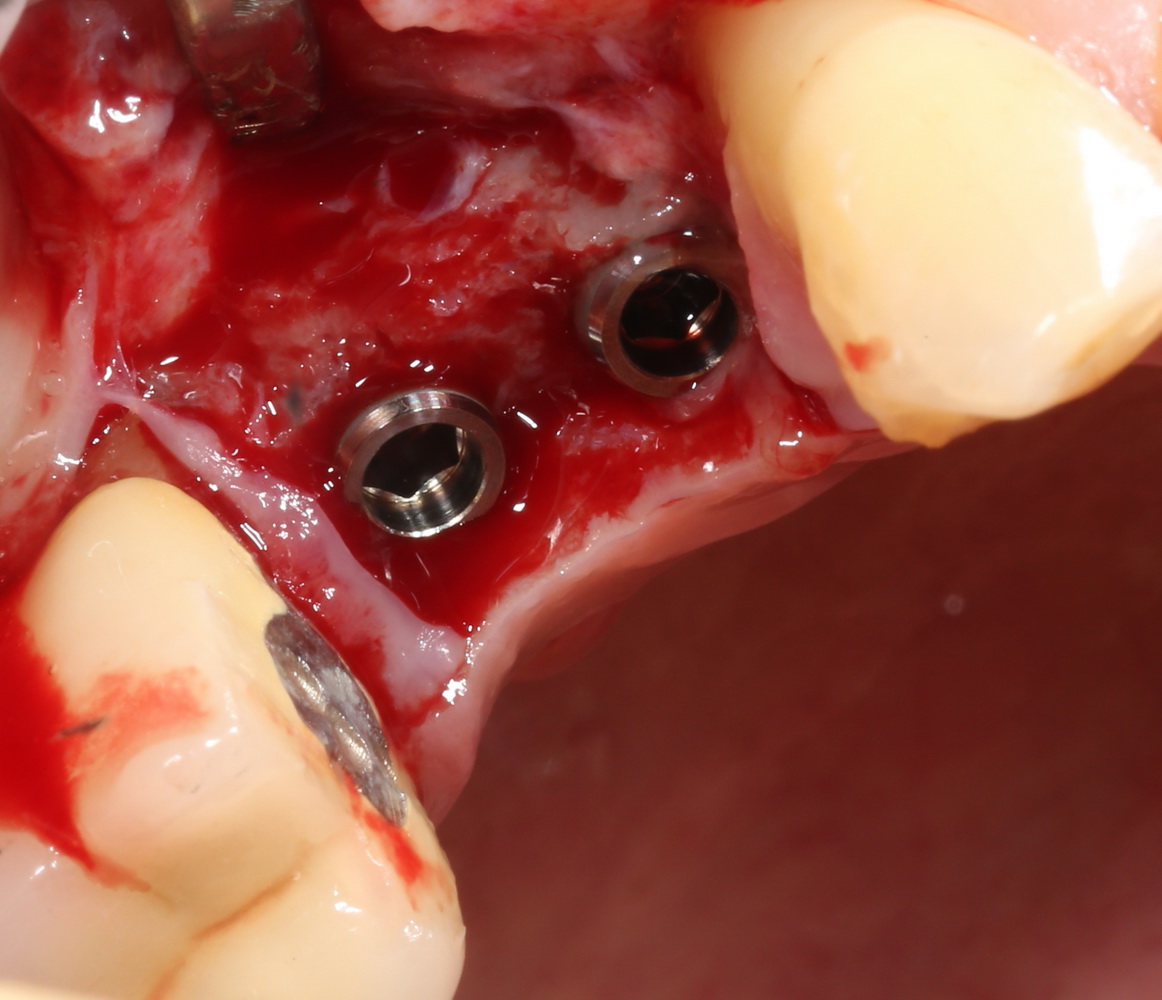

После установки второго импланта в правильное положение (ориентируемся по оси и форме лунки зуба), внешнюю кортикальную стенку восстанавливаем костным фрагментом, получившимся после синуслифтинга:

На деле — ничего сложного. Костный фрагмент просто фиксируется одним винтом. Таким образом восстанавливается отсутствующая костная стенка.

Субантральное пространство и пустые полости между костным блоком, имплантами и принимающим ложем заполняется аутокостной стружкой и закрывается мембраной BioGide: